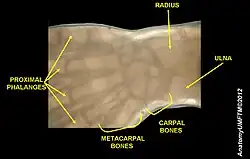

Carpometacarpal bossing (or metacarpal/carpal bossing) is a small, immovable mass of bone on the back of the wrist. The mass occurs in one of the joints between the carpus and metacarpus of the hand, called the carpometacarpal joints, where a small immovable protuberance[1] occurs when this joint becomes swollen or bossed.

The joint between the index metacarpal and the capitate is a fibrous non-mobile joint. Some people have a gene that leads to this growth. It looks like arthritis (bone spurs on each side of the joint) on X-ray. It looks like a ganglion on the hand, but more towards the fingertips.

The carpometacarpal joint is usually found at the base of the second and third metacarpal bones at the point where they meet the small bones of the wrist.[2]